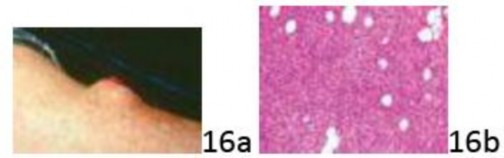

Question 16 A 45-year-old man has a 6-month history of a leg mass and recent ulceration of the skin. The clinical photograph and biopsy specimen are seen in Figures 16a and 16b. What is the most likely diagnosis?

Question 16 A 45-year-old man has a 6-month history of a leg mass and recent ulceration of the skin. The clinical photograph and biopsy specimen are seen in Figures 16a and 16b. What is the most likely diagnosis?

1. ## Ewing's sarcoma/peripheral primitive neuroectodermal tumor

2. ## Extraskeletal myxoid chondrosarcoma

3. ## Dermatofibrosarcoma

4. ## Myxoid/round cell liposarcoma

5. ## Synovial sarcoma

DISCUSSION: Dermatofibrosarcoma is a rare, monoclonal, cutaneous sarcoma arising in the dermis in the trunk, 47%; lower extremity, 20%; upper extremity, 18%; and head and neck, 14%. Symptoms may be present for a duration of 6 months to 30 years. It may occur at any age, with a peak incidence in the fourth decade; it is more common in men than women (3:2). Most tumors are superficial and less than 5 cm, but 3% are larger than 10 cm. They present early as pink or violet-red plaques surrounded by telangiectatic skin. A nodular growth pattern with ulceration and attachment to deeper structures is observed in advanced and/or recurrent cases.

Most cases (85% to 90%) are low grade but (5% to 15%) contain focal, high-grade fibrosarcomatous areas with intermediate-grade tumor (DFSP-FS). MRI is useful in ascertaining tumor extent and depth of invasion. Tumor cells exhibit a storiform growth pattern and infiltrate adjacent adnexal structures and adipose tissue.

Fibrosarcomatous transformation can occur over time and is recognized by

increased mitotic activity. Because some tumors express platelet derived growth factor, they may be responsive to imatinib. Ewing's sarcoma, extraskeletal myxoid chondrosarcoma, liposarcoma, and synovial sarcoma are generally deep-seated tumors that can but very rarely cause skin ulceration. The Preferred Resp# 16 is 3.

1. ## Ewing's sarcoma/peripheral primitive neuroectodermal tumor

2. ## Extraskeletal myxoid chondrosarcoma

3. ## Dermatofibrosarcoma

4. ## Myxoid/round cell liposarcoma

5. ## Synovial sarcoma

DISCUSSION: Dermatofibrosarcoma is a rare, monoclonal, cutaneous sarcoma arising in the dermis in the trunk, 47%; lower extremity, 20%; upper extremity, 18%; and head and neck, 14%. Symptoms may be present for a duration of 6 months to 30 years. It may occur at any age, with a peak incidence in the fourth decade; it is more common in men than women (3:2). Most tumors are superficial and less than 5 cm, but 3% are larger than 10 cm. They present early as pink or violet-red plaques surrounded by telangiectatic skin. A nodular growth pattern with ulceration and attachment to deeper structures is observed in advanced and/or recurrent cases.

Most cases (85% to 90%) are low grade but (5% to 15%) contain focal, high-grade fibrosarcomatous areas with intermediate-grade tumor (DFSP-FS). MRI is useful in ascertaining tumor extent and depth of invasion. Tumor cells exhibit a storiform growth pattern and infiltrate adjacent adnexal structures and adipose tissue.

Fibrosarcomatous transformation can occur over time and is recognized by

increased mitotic activity. Because some tumors express platelet derived growth factor, they may be responsive to imatinib. Ewing's sarcoma, extraskeletal myxoid chondrosarcoma, liposarcoma, and synovial sarcoma are generally deep-seated tumors that can but very rarely cause skin ulceration. The Preferred Resp# 16 is 3.